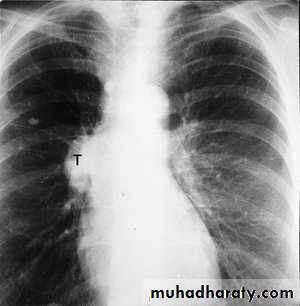

The main aims of investigations are to confirm the diagnosis, establish the histological cell type and define the extent of the disease.1-CXR: common radiological features of bronchial carcinoma;

Unilateral hilar enlargement.

Peripheral pulmonary opacity.

Lung, lobe or segmental collapse.

Pleural effusion.

Broadening of mediastinum, enlarged cardiac shadow, elevation of a hemidiaphragm.

Rib destruction.